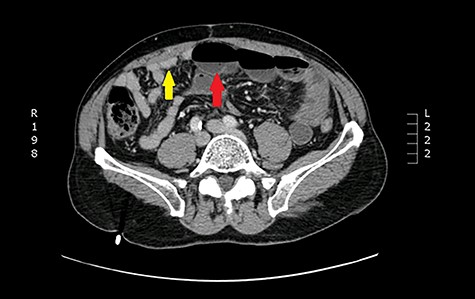

One year later, he was readmitted with small bowel obstruction investigated with an abdominal computed tomography (CT) scan that showed no radiological finding of stenotic Crohn disease or other obstructive etiology (Figs 2 and 3).

Axial view: arrows pointing to dilated and collapsed small bowel.